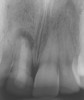

To achieve an esthetic result, it is advantageous to have papillary symmetry between contralateral sides of the dentition and avoidance of short papillae between implants. Tarnow et al67 demonstrated that implants should be placed at least 3 mm apart to avoid bone loss, which can result in recession of papillae. In a later study, Tarnow and colleagues68 noted that the average height of a papilla between two implants was 3.4 mm and that > 50% of the papillae between implants were ≤ 3 mm in height (Figure 4).68 Therefore, to attain the best esthetics, if two adjacent implants are to be placed, modification of the treatment plan may be necessary. If possible, consideration should be given to saving one tooth to avoid short papillae.

Figure 4  The average height of a papilla between 2 implants is 3.4 mm. Note the short papilla between implant-supported crowns on teeth Nos. 9 and 10.

Figure 4